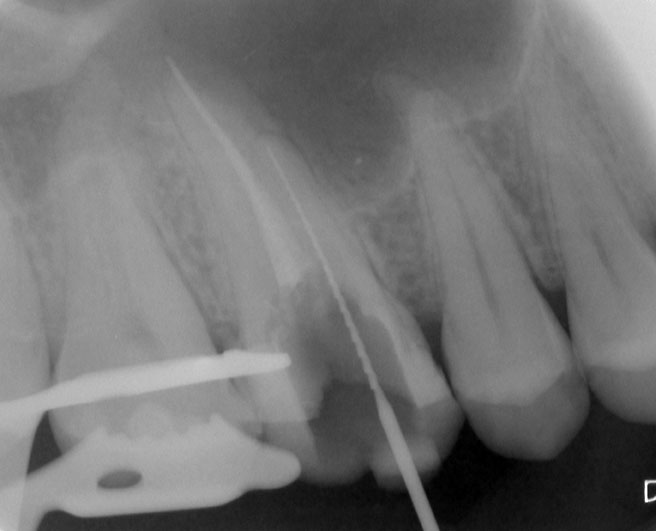

Nach erfolgter Information über die vermutete Prognose unternehmen wir den Versuch, das frakturierte Instrument darzustellen. Nach Entfernung der Aufbaufüllung werden die Kanaleingänge dargestellt (Abb. 2). Es zeigt sich, dass neben dem distovestibulären Kanal auch ein vierter Kanal (mb2) vorhanden ist. Die Darstellung der Wurzelkanaleingänge erfolgt in unserem Haus mit dem Aufsatz 1R des Tigon+. Dank der Abwinkelung des Instruments profitiert man von einer sehr guten Sicht auf die Behandlungsstelle. Zudem erlaubt es ein schnelles und gezieltes Abtragen von Dentin, ohne dabei den Zahn unnötig zu schwächen.